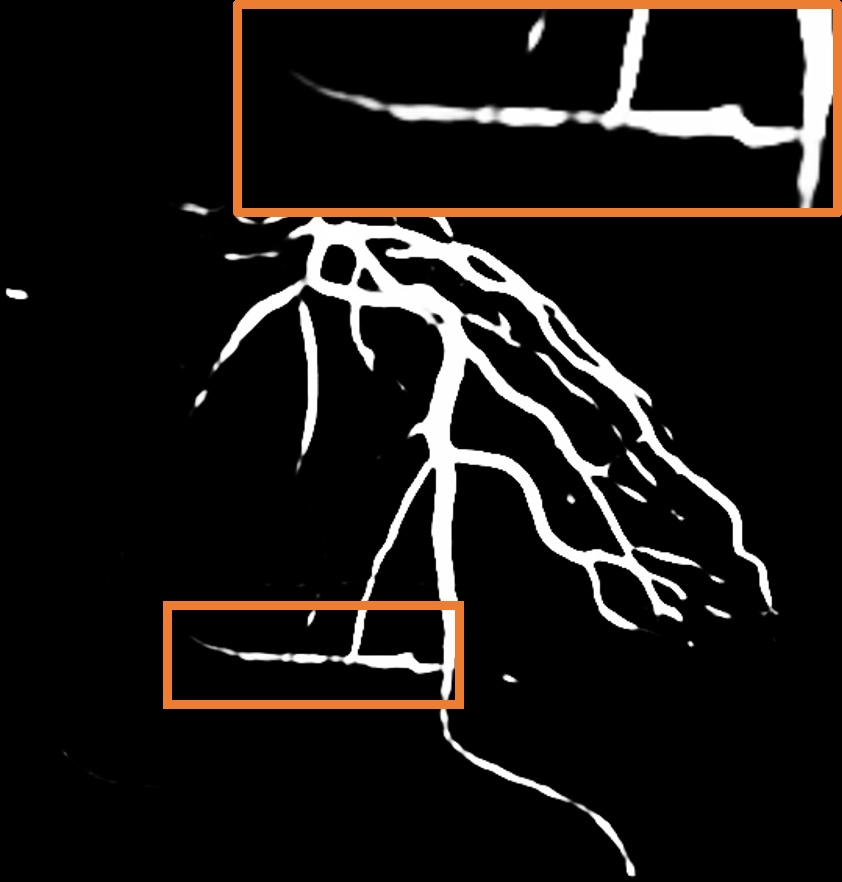

A.2 Temporal Coherency

Our method takes an entire X-ray video as input, thus producing segmentation results with better temporal coherency. Temporal coherency is essential for making medical diagnoses, especially when dealing with blood flow in vessels. Therefore, we conduct visual comparisons between our method and other compared methods by slicing horizontally or vertically and stacking the segmentation results. The results in Figure 11 show our method strikes a better balance between segmentation accuracy and temporal coherency. While other baseline methods either produce false segmentation results or do not maintain consistent prediction along the temporal dimension.